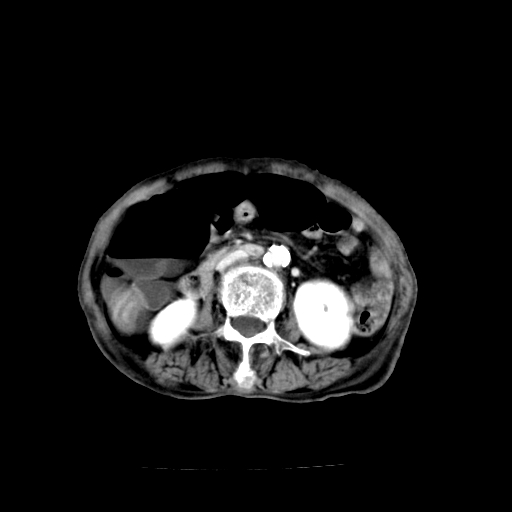

标题: CT19149:女,68岁,腹胀、恶心两周。 [打印本页]

标题: CT19149:女,68岁,腹胀、恶心两周。

女,68岁,腹胀、恶心两周,先做ct平扫,当时家属不同意强化,6天后家属要求增强扫描。